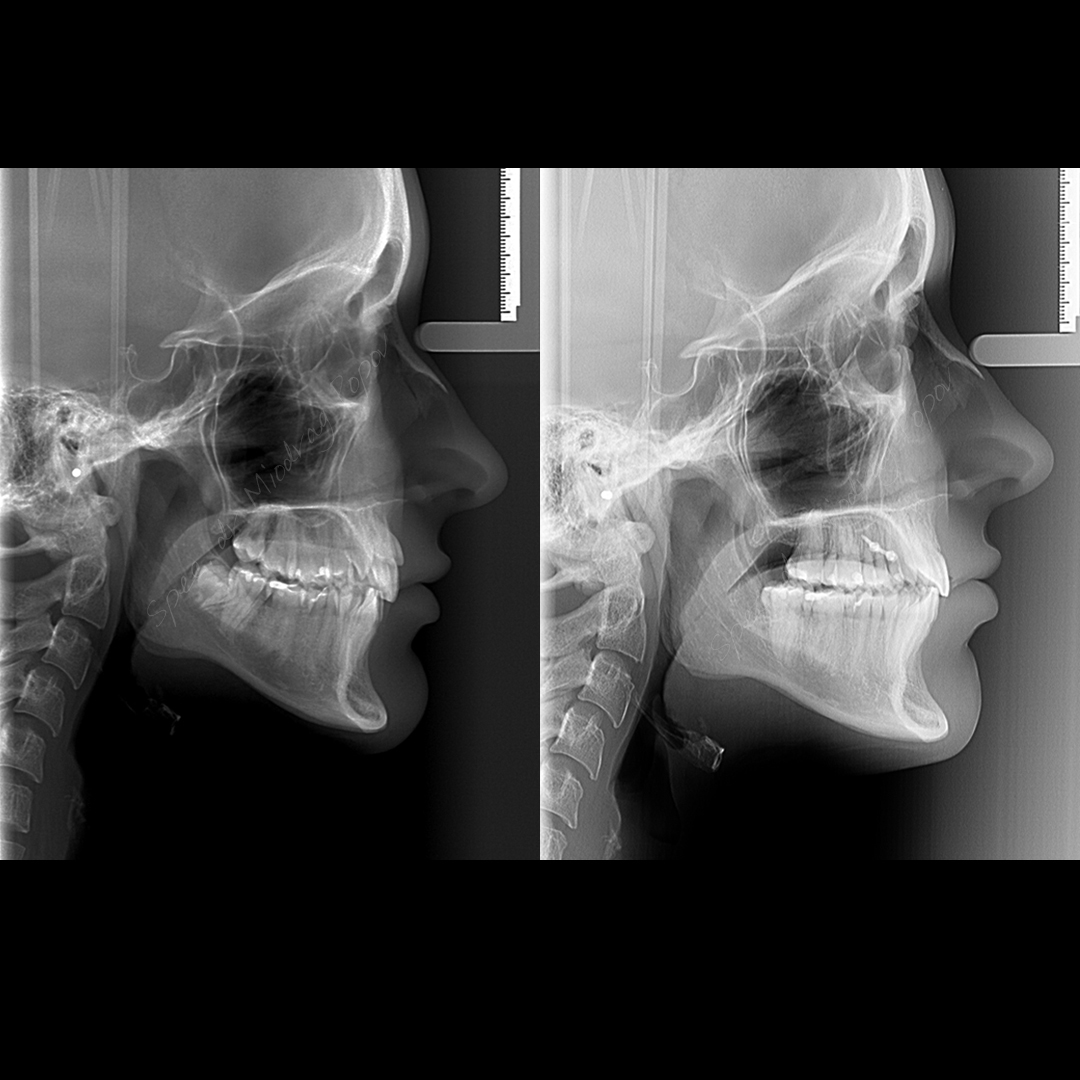

Danas predstavljamo slučaj gde je ektopično, bukalno postavljen očnjak – vidljiv pri osmehu, uspešno vraćen u zubni niz.

Bitno je istaći da je uz precizno vođenu mehaniku i upotrebu konzole i mini implantata, postignut fenomenalan estetski rezultat.

Pacijentkinjin profil je ostao nepromenjen, dok je osmeh postao još lepši i prirodniji!